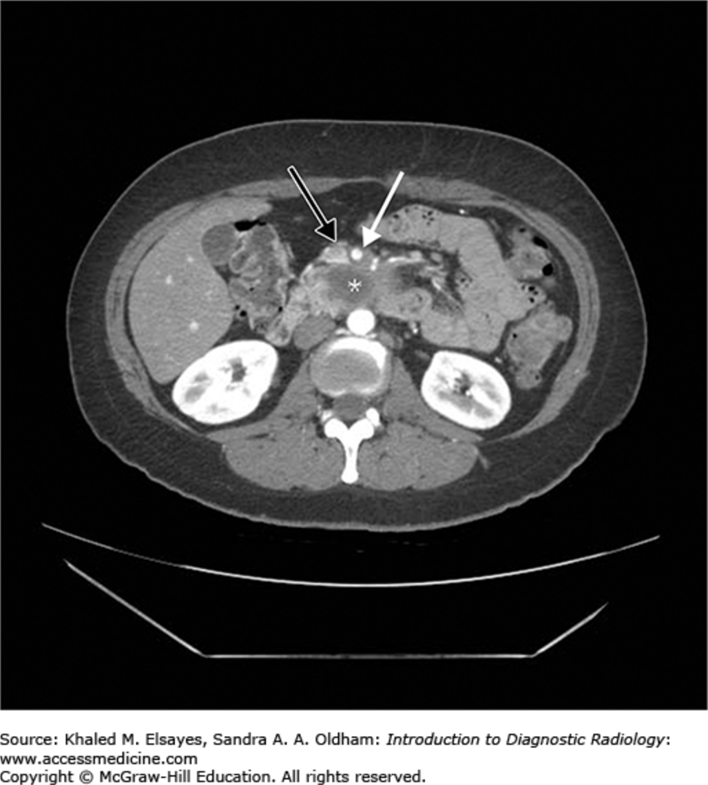

pancreatic adenocarcinoma. SMV abutted but not encased

pancreatic adenocarcinoma